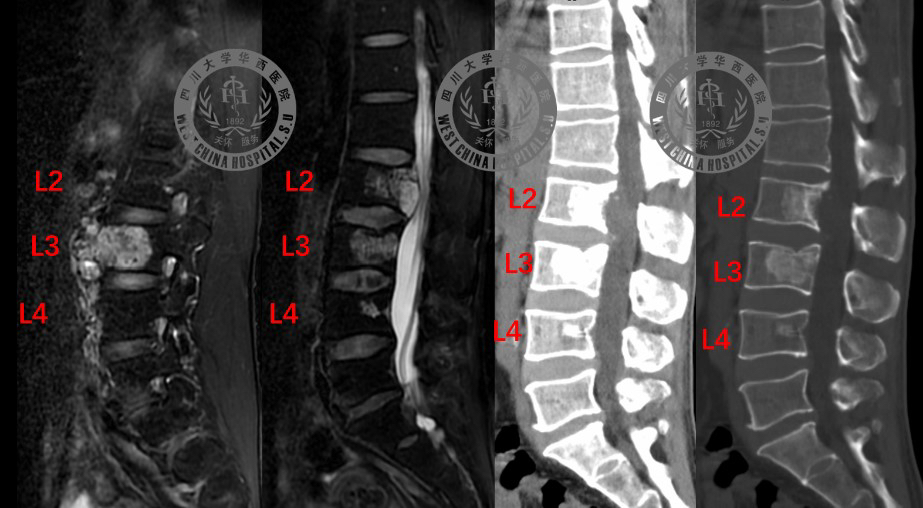

世界级难度!长满肿瘤的腰椎椎骨被整块切除,医院用3D打印技术为他重建 2022年05月13日 18:53